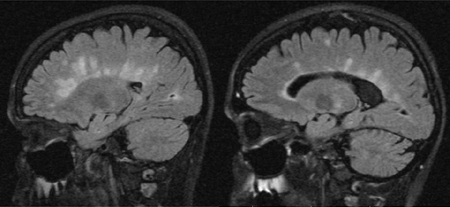

საგიტალური სითხით-გაძლიერებული ინვერსიული აღდგენის (FLAIR) სურათები დაგვეხმარება თეთრი ნივთიერების არასპეციფიკური ცვლილებების შესადარებლად გაფანტული სკლეროზის დაზიანებებთან. არასპეციფიკური ცვლილებები გვხვდება ჰიპერტენზიის, დიაბეტის, >50 ასაკის, მოწევის, შაკიკის, მაღალი ქოლესტერინის და ტოქსინებზე ექსპოზიციის დროს.[Figure caption and citation for the preceding image starts]: საგიტალურ ჭრილში FLAIR სურათები გაფანტული სკლეროზისთვის დამახასიათებელი დაზიანებებით, რომლებიც მოიცავენ კორძიან სხეულს გამოკვეთილი დაზიანებების სახით ან წარმოადგენენ თითისმაგვარ შვერილებს კორძიანი სხეულის პერპენდიკულარულად. ასევე მიაქციეთ ყურადღება დილატირებულ პარკუჭებს და უფრო ღრმად განვითარებული გაფანტული სკლეროზის დიფუზურ ატროფიასFrom the collection of Dr Lael A. Stone [Citation ends].